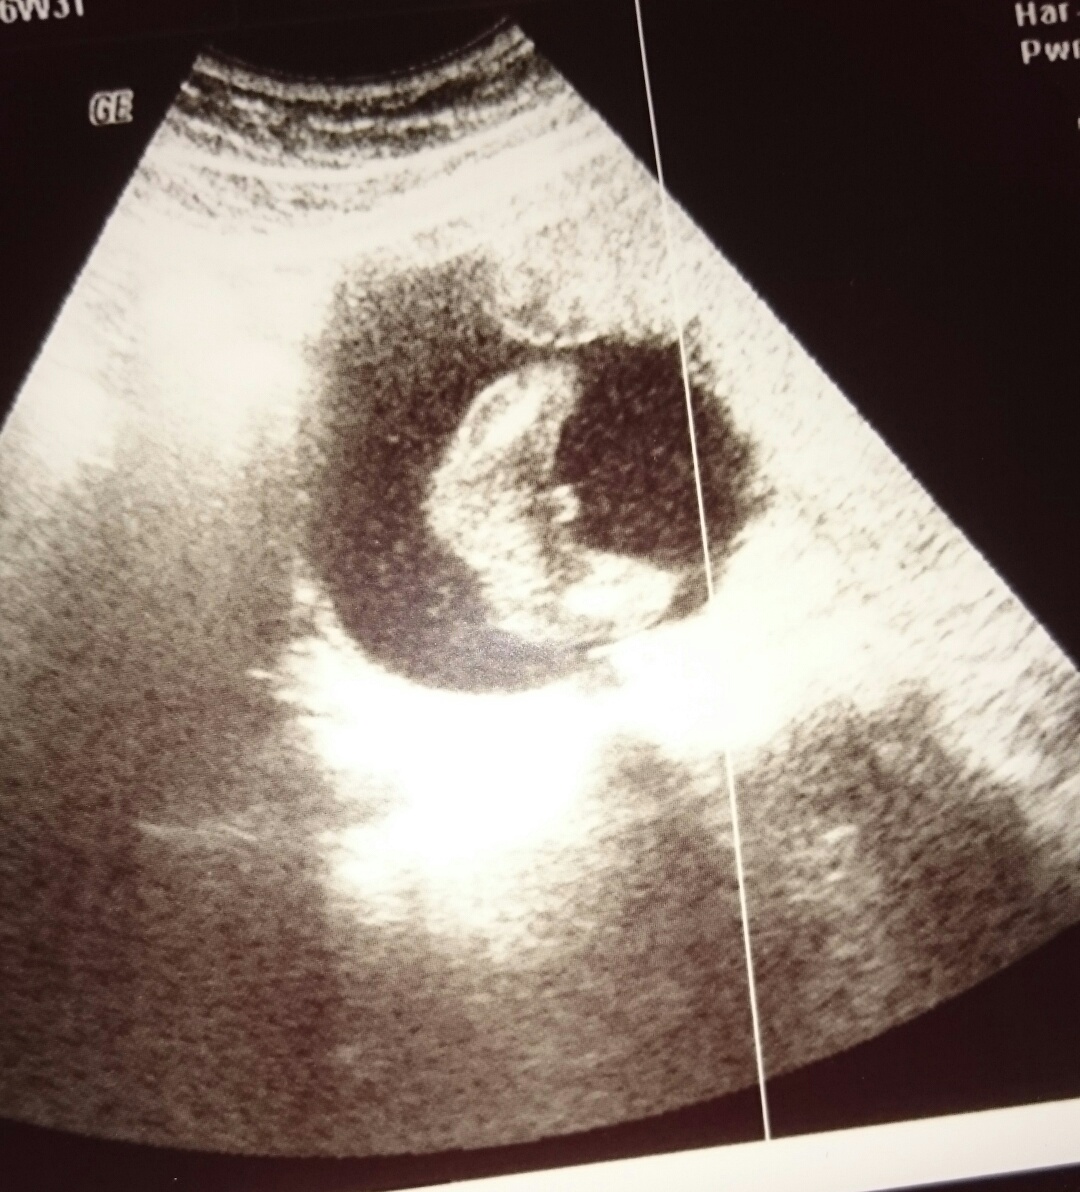

Hallo Ihr Lieben, für alle UltraschallGeschlechtserkennerExperten unter Euch Erkennt man auf dem US schon das Geschlecht des Baby?. Viele sagen, dass man erst nach der 18 SSW das Geschlecht erkennen kann Gibt es eine Garantie?. Alles Wissenswerte rund um die Geschlechtsbestimmung beim Baby 40 Wochen trägt die Mutter ihr Kind in ihrem Bauch.

Geschlecht erkennbar Ultraschall ?. 13 SSW Hallo ihr, normal bin ich immer stiller Mitleser, aber diesmal will ich auch mal eure Meinung hören Ich bin aktuell 124 und hab dieses Ultraschallbild heute erhalten Meine Ärztin meint, sie kann noch kein Geschlecht erkennen. Ultraschall 16 ssw mädchen Riesenauswahl an Markenqualität Ulraschall gibt es bei eBay SSW Geschlecht unter dem Ultraschall erkennen Bei einer Routineuntersuchung bei Ihrem Frauenarzt in der 16 SSW könnte es endlich so weit sein und Sie könnten endlich erfahren, was für ein Geschlecht Ihr Baby haben wird.